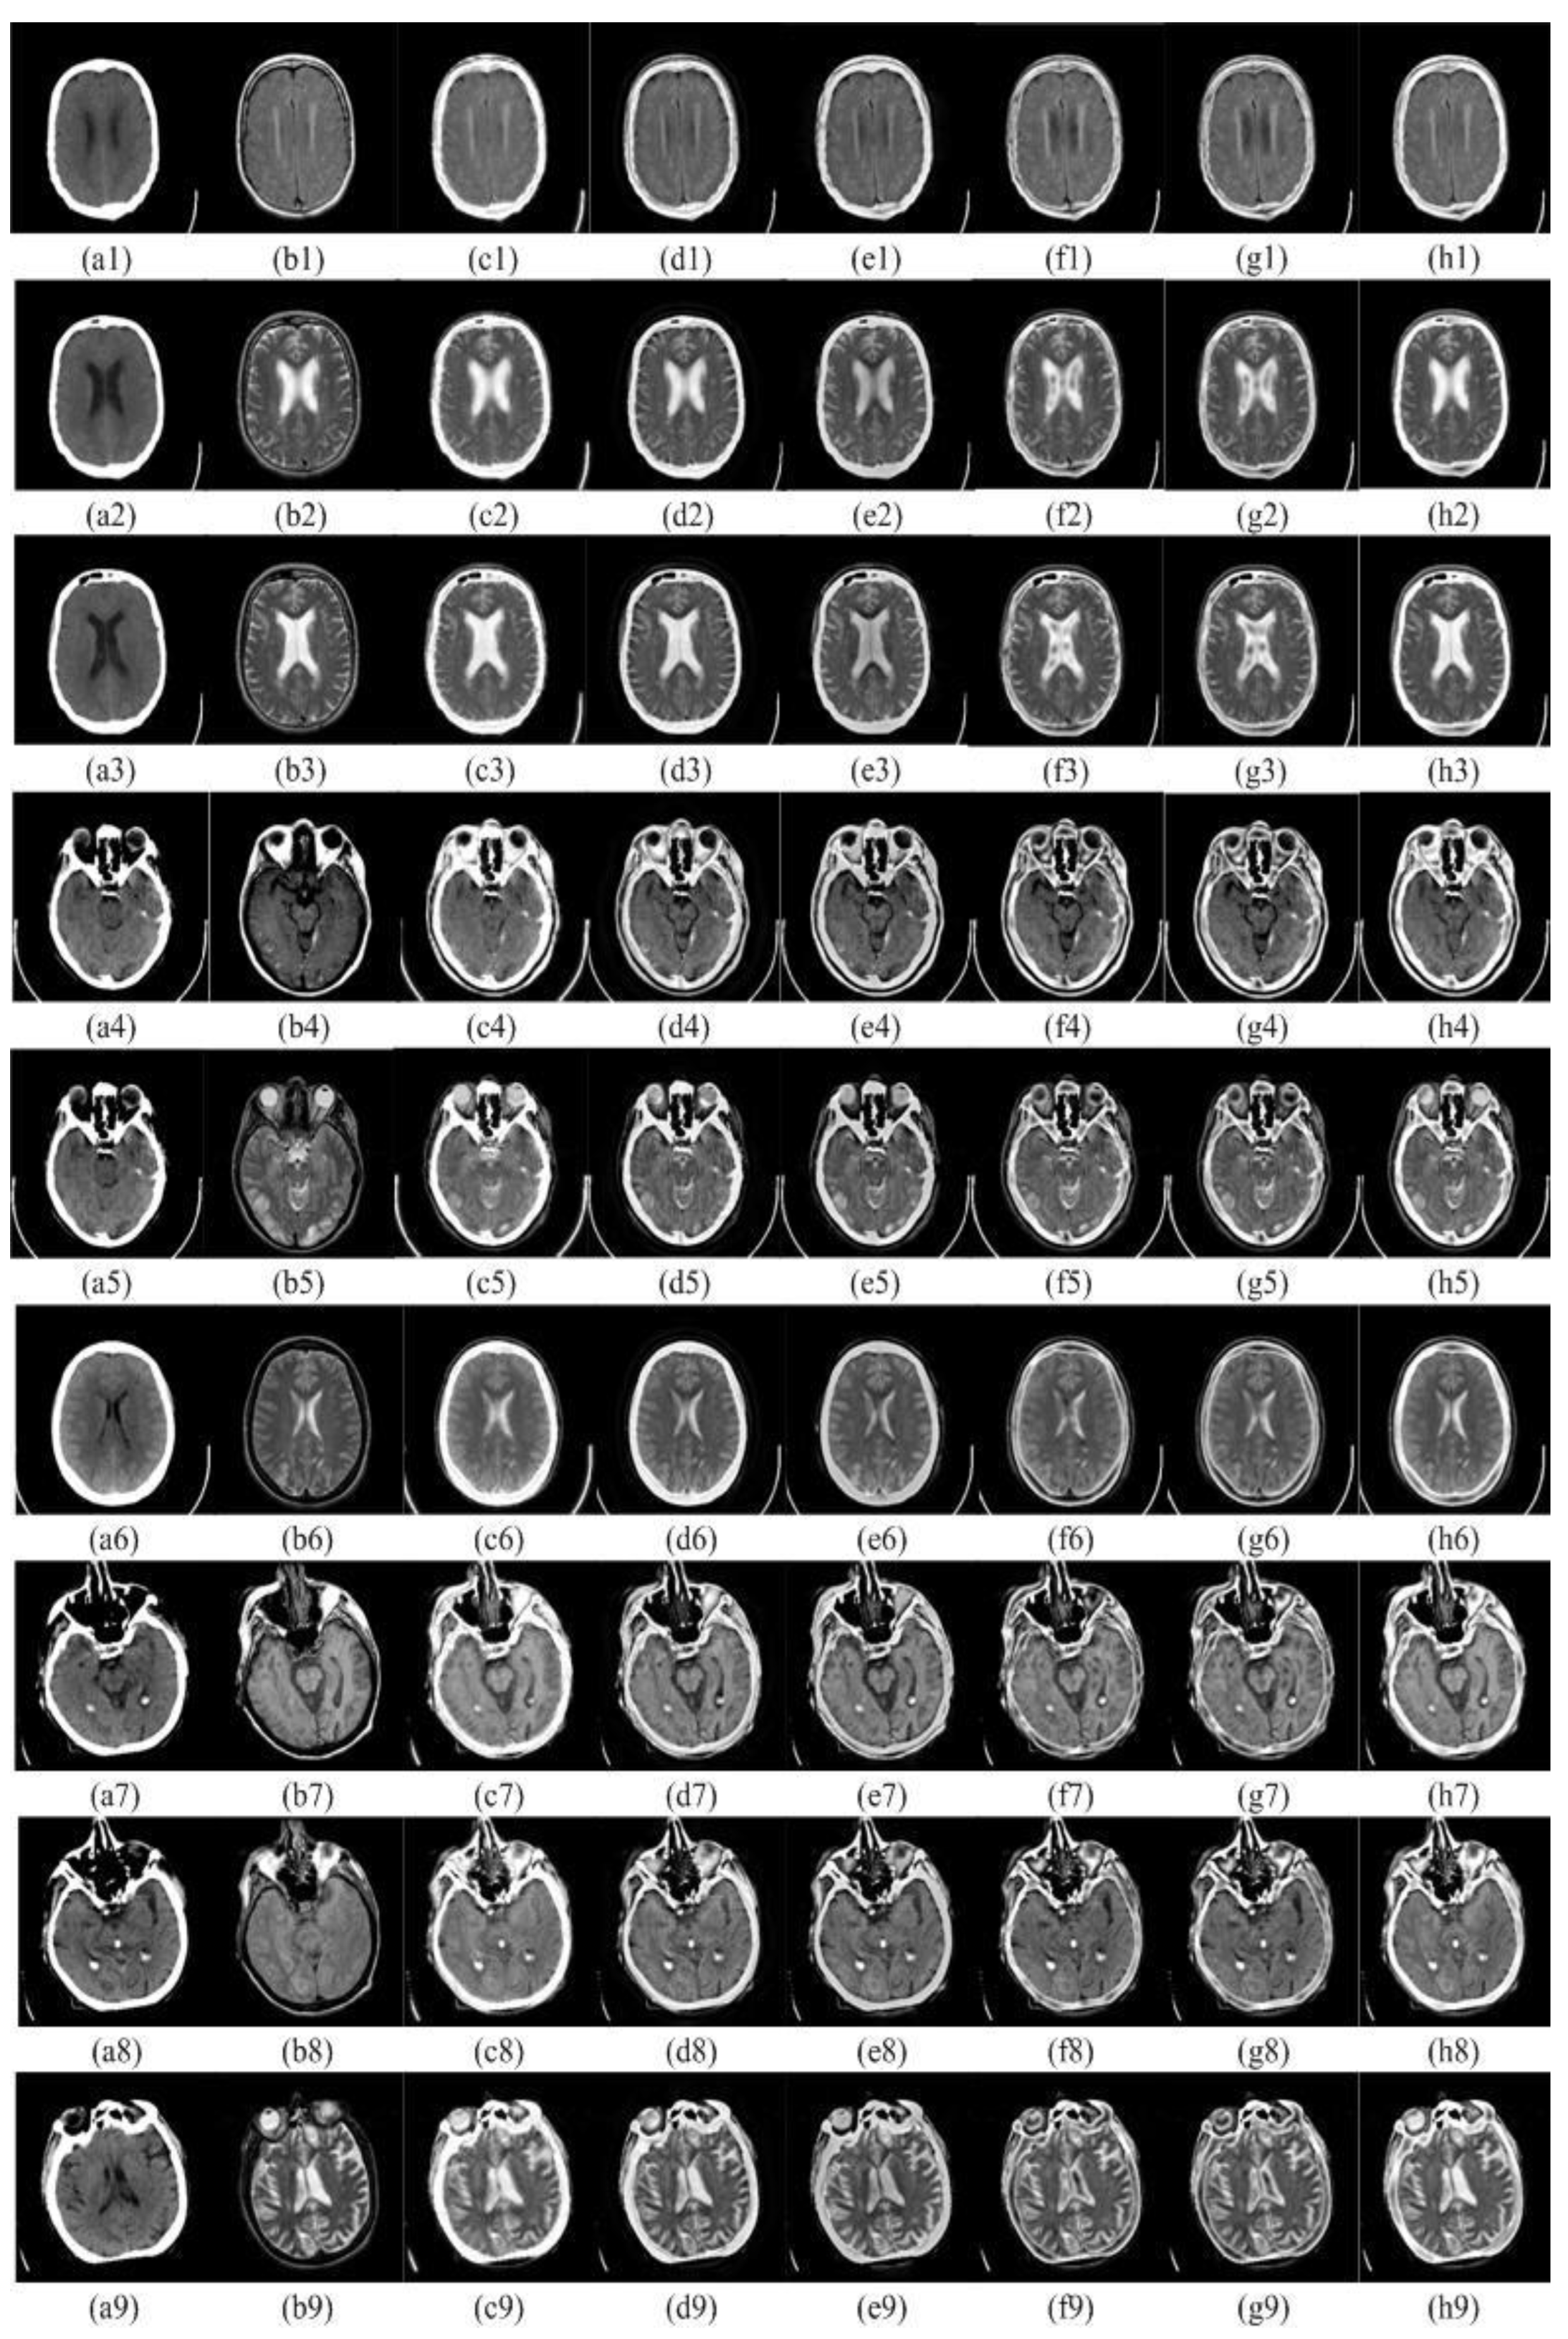

4.2.1. Subjective Visual Evaluation